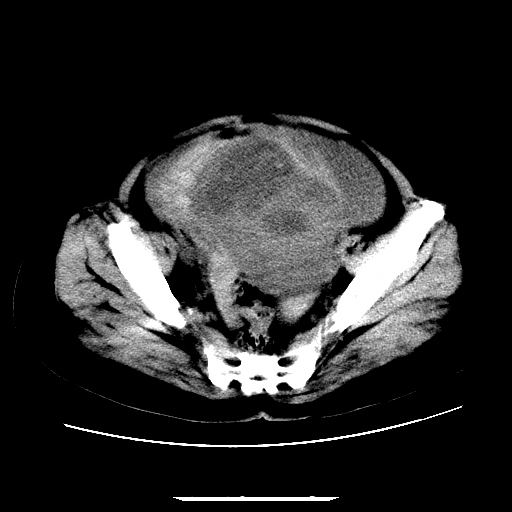

f,45y.怀孕4月晕倒,b超提示死胎,有手术结果,请展开讨论后明天告诉。

膈下-肠间隙内见气体密度影,子宫轮廓显示不清,宫腔-腹腔积液,首选考虑---子宫破裂出血。

1)宫腔妊娠。2)子宫破裂出血,腹腔及盆腔积血。

怀孕4个月晕倒,病史就这么简单?有没有腹痛呢?腹腔内有没有气体?窗宽太窄了脂肪组织与气体已不好分。如果有气体,那就是空腔脏器穿孔,如胃肠穿孔。如没有气体,就考虑子宫破裂或宫外孕破裂。正常怀孕子宫破裂很少见,有可能是宫外孕。极有可能是残角子宫怀孕破裂。腹腔怀孕破裂也有可能。

感谢同行们的高见。手术结果:子宫破裂出血。

我们的诊断是:腹、盆腔积液(考虑腹盆腔脏器破裂出血);宫腔妊娠。让人纳闷的是当时我们没有经验,现在回头看看分析:4月宫腔妊娠:1、洋膜囊不可能紧贴胎体这么小;2仔细看看子宫后壁肌层模糊不清;3腹、盆腔液体来源原因?4、45岁高龄妊娠有晕倒。由此可大胆诊断:宫腔妊娠子宫破裂出血。